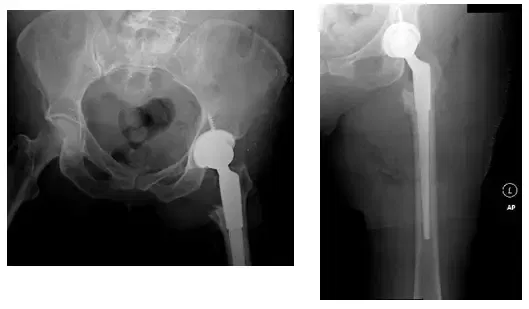

Post-operativeX-Rays show removal of hardware and left THA with long stem femoral prosthesis

Patient came in post-operatively with no pain, good range of motion, and was weight bearing as tolerated. Patient has been doing well subsequently.